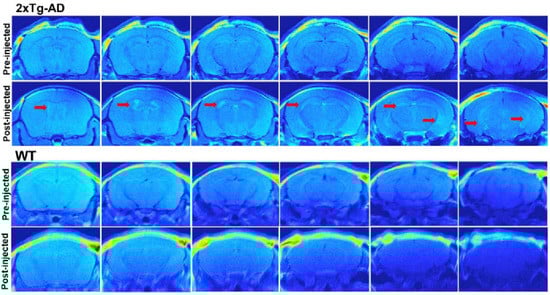

- Yanagisawa, D.; Amatsubo, T.; Morikawa, S.; Taguchi, H.; Urushitani, M.; Shirai, N.; Hirao, K.; Shiino, A.; Inubushi, T.; Tooyama, I. In Vivo Detection of Amyloid β Deposition Using 19F Magnetic Resonance Imaging with a 19F-Containing Curcumin Derivative in a Mouse Model of Alzheimer’s Disease. Neuroscience 2011, 184, 120–127. [Google Scholar] [CrossRef] [PubMed]

- Yanagisawa, D.; Ibrahim, N.F.; Taguchi, H.; Morikawa, S.; Tomiyama, T.; Tooyama, I. Fluorine-19 Magnetic Resonance Imaging for Detection of Amyloid β Oligomers Using a Keto Form of Curcumin Derivative in a Mouse Model of Alzheimer’s Disease. Molecules 2021, 26, 1362. [Google Scholar] [CrossRef] [PubMed]